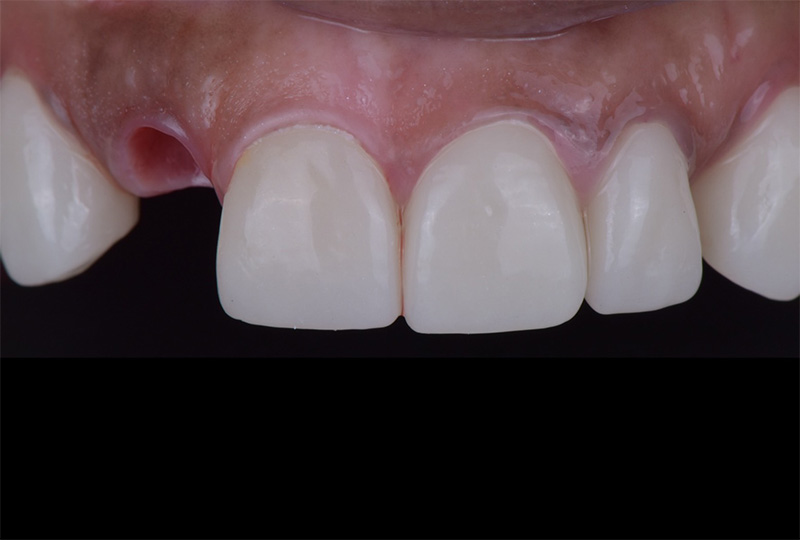

• 治療前

• 治療後

症例名 被せ物の下が虫歯になり折れてしまい、抜歯適応になってしまった歯をインプラントを抜歯と同時に埋入する事で、インプラントにより審美面機能面で回復を行った症例

主訴/ニーズ 被せ物が外れた。できれば元通りに直して欲しい。人前に立つ職業なので、見た目が自然なのが1番大事。

治療内容 この患者様は、被せ物が取れてしまったため再装着を希望されて来院されました。 しかし、診査の結果、被せ物の土台となる歯根が折れており、残念ながら抜歯以外の選択肢がない状態でした。見た目や機能、そして長期的な安定性を考慮したうえで、今回は抜歯と同時にインプラントを埋入する「抜歯即時インプラント」を行いました。 この方法を選択することで、治療期間を大幅に短縮できるだけでなく、周囲の歯ぐきの退縮を最小限に抑え、より自然で美しい仕上がりが期待できます。 抜歯即時インプラントは、すべてのケースで行えるわけではなく、適応症の見極めが非常に重要です。この患者様の場合、骨の状態や感染の有無などを慎重に確認したうえで、適応可能と判断し実施しました。結果として、見た目・機能ともに良好な経過を得ることができました。患者様も結果に非常に満足されました。